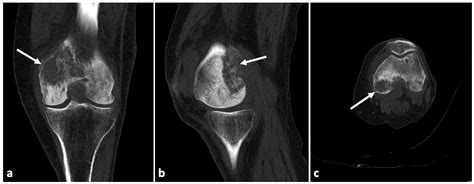

• Imaging Tests: X-rays, MRI, or ultrasound may be used to visualize the joint and assess the extent of fluid buildup.